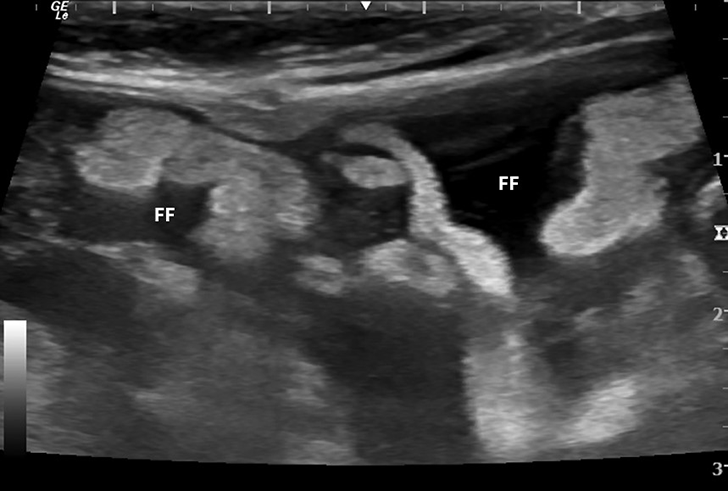

Kidney of a cat with non effusive FIP. Granulomatous lesions can sales, Cat kidneys. A Multifocal to coalescing granulomatous sales, Conference 25 2013 Case 02 20140507 sales, Viruses Free Full Text Feline Infectious Peritonitis European sales, Feline Infectious Peritonitis an overview ScienceDirect Topics sales, History of Feline infectious Peritonitis 1963 2022 First sales, Renal FIP sonographic features Vet Practice Support sales, Feline Infectious Peritonitis Virus Infection sales, Renal FIP sonographic features Vet Practice Support sales, Renal FIP sonographic features Vet Practice Support sales, Kidney of cat infected naturally with effusive FIP showing sales, Kidney FIP capsule removed from kidney on the left in Cats sales, History of Feline infectious Peritonitis 1963 2022 First sales, A new perspective on the pathogenesis of chronic renal disease in sales, Prevalence and clinical significance of the medullary rim sign sales, Figure 4 from FIP and infectious neurological diseases of the cat sales, Viruses Free Full Text Feline Infectious Peritonitis European sales, Renal FIP sonographic features Vet Practice Support sales, Ultrasonography of the feline kidney sales, Sagittal ultrasound scan of the left kidney of a cat with feline sales, Noninfectious Diseases of the Urinary System of Cats Cat Owners sales, FIP Treatment Tip Pay Attention to Liver and Kidney sales, What s Your Diagnosis Signalment 8 mo MC DSH Presenting sales, Ultrasonography of the Urinary Tract Kidneys and Ureters sales, Feline abdominal ultrasonography what s normal what s abnormal sales, PDF Diagnosis of feline infectious peritonitis Update on sales, SciELO Brasil Causes of death and euthanasia in domestic cats sales, Complete Guide to Feline Infectious Peritonitis FIP sales, June s Case of the Month MivuDC sales, Feline Infectious Peritonitis sales, Feline infectious peritonitis Wikipedia sales, International Pharmaceutical Federation FIP on LinkedIn Chronic sales, Feline Infectious Peritonitis Cornell University College of sales, June s Case of the Month MivuDC sales, Complete Guide to Feline Infectious Peritonitis FIP sales.

Fip kidney sales